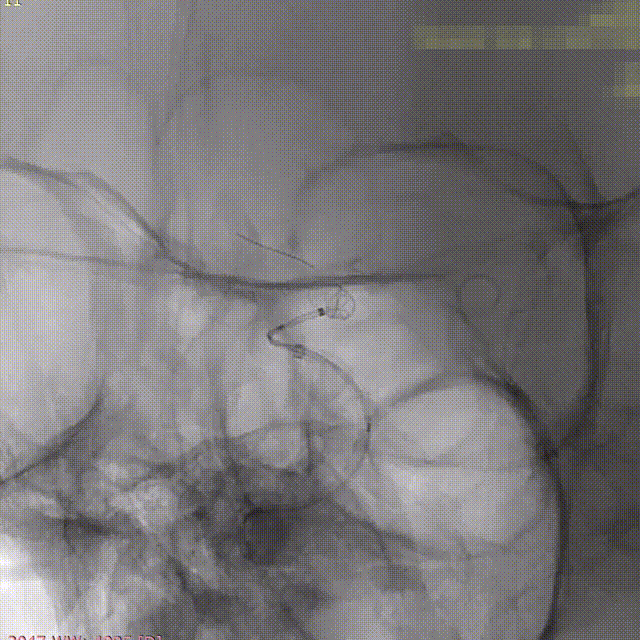

术后即刻造影。

术后重建。

术后小结

强易达(Choydar)血流导向密网支架头端封闭结构,减少对血管壁的损伤,安全性好。

独特热处理技术增强了贴壁性。整体释放操作简单,无需过多推挤,显影清晰。

强易达(Choydar)血流导向密网支架2-3mm直径可通过其0.017微导管输送系统释放,通过性好,在此病例中也减少了更换微导管带来的操作和风险。

强易达(Choydar)血流导向密网支架打开贴壁良好,2mm和3mm支架在不同血管直径中均展现了良好的贴壁,小血管中表现优异。2mm-6.5mm直径可选,型号多,应用范围广。